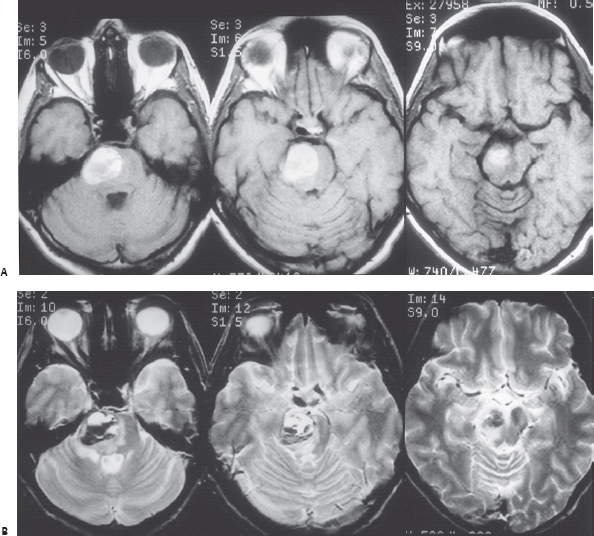

图17.5:磁共振成像(MRI)对一名34岁女性患者进行了1周的病史,突然出现左侧无力和感觉丧失,其结果与脑桥海绵状血管瘤引起的大面积亚急性出血一致。注意,大部分亚急性出血—(A)T1加权和(B)T2加权图像上的高信号强度区域—位于(B)T2加权图像上病变囊(低信号强度环)的正常范围之外。这种模式和(B)T2加权图像上水肿的存在与“大出血”或病灶外出血一致,并且与复发性症状性出血的相关。较近的亚急性出血区域到达脑桥腹侧的软脑膜表面,为手术切除病变提供了顺利的途径。经眶颧入路清除血肿及相关海绵状血管瘤,无并发症,患者术后1周出院,情况良好。在2年的随访中,患者无症状,没有复发性出血或残留病变(C) 该患者术后二天获得的T2加权自旋回波图像显示术后早期MRI研究难以解释;手术床上的水肿和血液容易与残留的海绵状血管瘤相混淆(D) 术后6个月的重复MRI仅在T2加权自旋回波图像上显示含铁血黄素与慢性溶解性出血相关的特征性低信号特征。延迟图像上该区域内没有任何高信号区域证实海绵状血管瘤完全切除。

出血率在急性/亚急性出血发作侵犯病变囊的患者中似乎特别高,产生所谓的“显性”病变外出血(IA型病变;图17.5A,B)进入周围大脑。Aiba和同事39对62例此类患者进行了平均3.12年的随访,发现每年复发症状性出血的风险为22.3%。Barker和同事42报道了选择141名出现“明显”出血的患者进行干预的类似经历。在这个系列中,63名患者在治疗前经历了二次出血。出血集中在初始事件周围,前28个月每年再出血率为25.2%。据报道,海绵状血管瘤不完全切除后再出血的发生率相当,可能是由于病变囊中断所致,强调了在初始手术过程中完全切除的重要性。